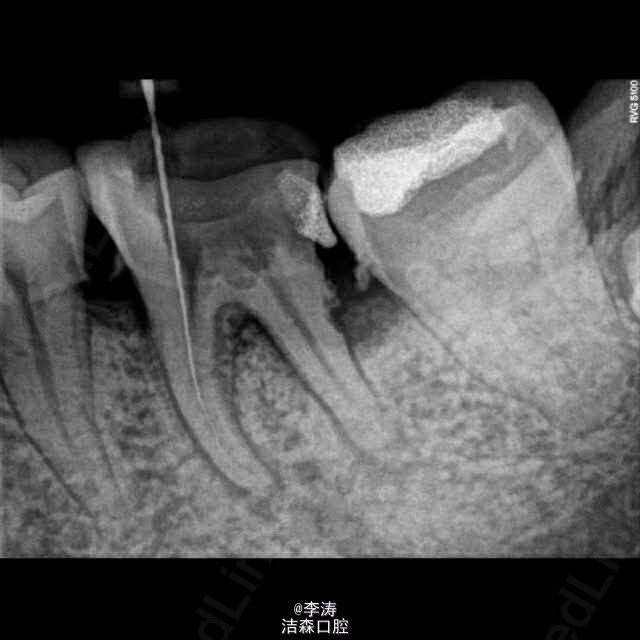

根管预备形成台阶1例

36牙根管治疗,近中根略弯曲,先疏通至15号,k3冠向下法预备,预备时形成台阶,然后怎么预弯都下不去! 太弯根管的还是应该使用手扩,特别是k3,弯曲根管尽量不用,容易形成台阶。另外预备过程中不能使用暴力!!